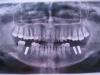

Lacerta Опубликовано 11 марта, 2010 Поделиться Опубликовано 11 марта, 2010 (изменено) Здравствуйте, уважаемые доктора! Около 6 лет назад были удалены обе шестерки снизу; 1,5 года назад - левая нижняя семерка (кисты и гранулемы после не очень удачного лечения в детстве).В начале фервраля удалили ретинированные восьмерки снизу и в конце февраля мне одномоментно поставили 3 импланта (Astra Tech), заранее предупредив, что, возможно, придется депульпировать и убрать под коронку верхнюю шестерку слева, так как места для коронки на имплант осталось очень мало (шестерка выдвинулась вниз после потери зуба-антагониста). Послеоперационный период гладкий. Мой хирург - доктор очень хороший и замечательный, именно он мне удалял почти все зубы и потом занимался имплантацией, мое отношение к нему исключительно уважительное и доверительное. В мае мне предстоит протезирование; меня же сильно волнует судьба моей верхней шестерки. Как видите - у меня и так проблемы с молярами (тут горючие слезы), и депульпировать еще один очень жалко. Доктор мой в сомнениях (больше склоняется к коронке) и предлагает показаться протезисту ближе к моменту протезирования. Разумеется, без протезиста мне не обойтись , но я была бы вам благодарна за независимое мнение - можно ли поставить протез на имплант без "коронации" шестерки?. Фотографии прикладываю (ортопантограмма через пару дней после имплантации и прикус в проблемной зоне в разных ракурсах - в отдельной ссылке). Заранее спасибо! Прикус - тут: http://1rd.spb.ru/images/pricus.jpg Изменено 11 марта, 2010 пользователем Lacerta Ссылка на комментарий

Премоляр Опубликовано 12 марта, 2010 Поделиться Опубликовано 12 марта, 2010 Спасибо большое за перенос! Возникли вопросы к уважаемым ортодонтам. Возможно ли ортодонтическое лечение в моем случае? Будет ли система крепиться за верхние восьмерки? Восьмерки планируется впоследствии на удаление, так как постепенно разрушаются.Достаточно ли брекет-системы только на одну верхнюю челюсть? Извините за этот типичный пациентский вопрос. Мне хочется верить, что это возможно в моем случае, ведь прикус в передней части правильный, нарушения только сзади, то есть там, где снизу антагонистов вообще нет.И если лечение возможно, то я ищу ортодонта в Питере. Фотоматериалы находятся в начале темы.Фото прикуса "анфас" тут - http://1rd.spb.ru/images/anfas.jpgСпасибо, что отвечаете на вопросы! 1-Сначала надо было с ортодонтом проконсультироваться...2-Фото в прикусе не информативно,надо в боковом отделе3-конечно реально внедрить зубы на микроимплантах.Но необходимы окклюз.фото для точного плана лечения.Не торопитесь точить зубы,сходите к ортодонтуhttp://s61.radikal.ru/i171/1003/ad/1a16f611091b.jpgкорни в пазухе. Ссылка на комментарий